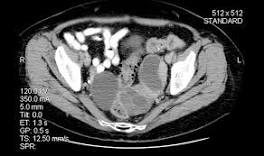

| What next? Not sure if this is from being in the bed all the time or cancer spreading to these areas. Scheduled for a CT of the lungs on Jan.4th so I have requested ...